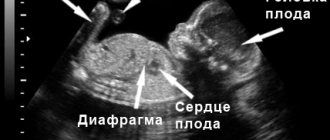

Осложнения отражаются не только на беременной, но и на ребенке. Плод на 24 неделе беременности наиболее подвержен патогенным факторам. Именно поэтому во втором триместре важно пройти ультразвуковую диагностику, чтобы исключить пороки развития. Врач посмотрит, как развиваются органы у малыша, проанализирует параметры кровотока в пуповине, матке, у плода.

11. При диагностике на головном мозге уже виднеются бороздки, извилины, мозжечок со средним отделом мозга практически сформирован.

В этом случае следует обратиться к врачу или в роддом (если это ночное время или выходной) для контроля записи сердцебиения плода на специальном аппарате КТГ. При необходимости на 24 неделе беременности выполняется УЗИ с допплерометрией. Последнее позволяет оценить скорость кровотоков в сосудах плаценты, пуповины, плода и дать заключение о внутриутробном состоянии малыша.